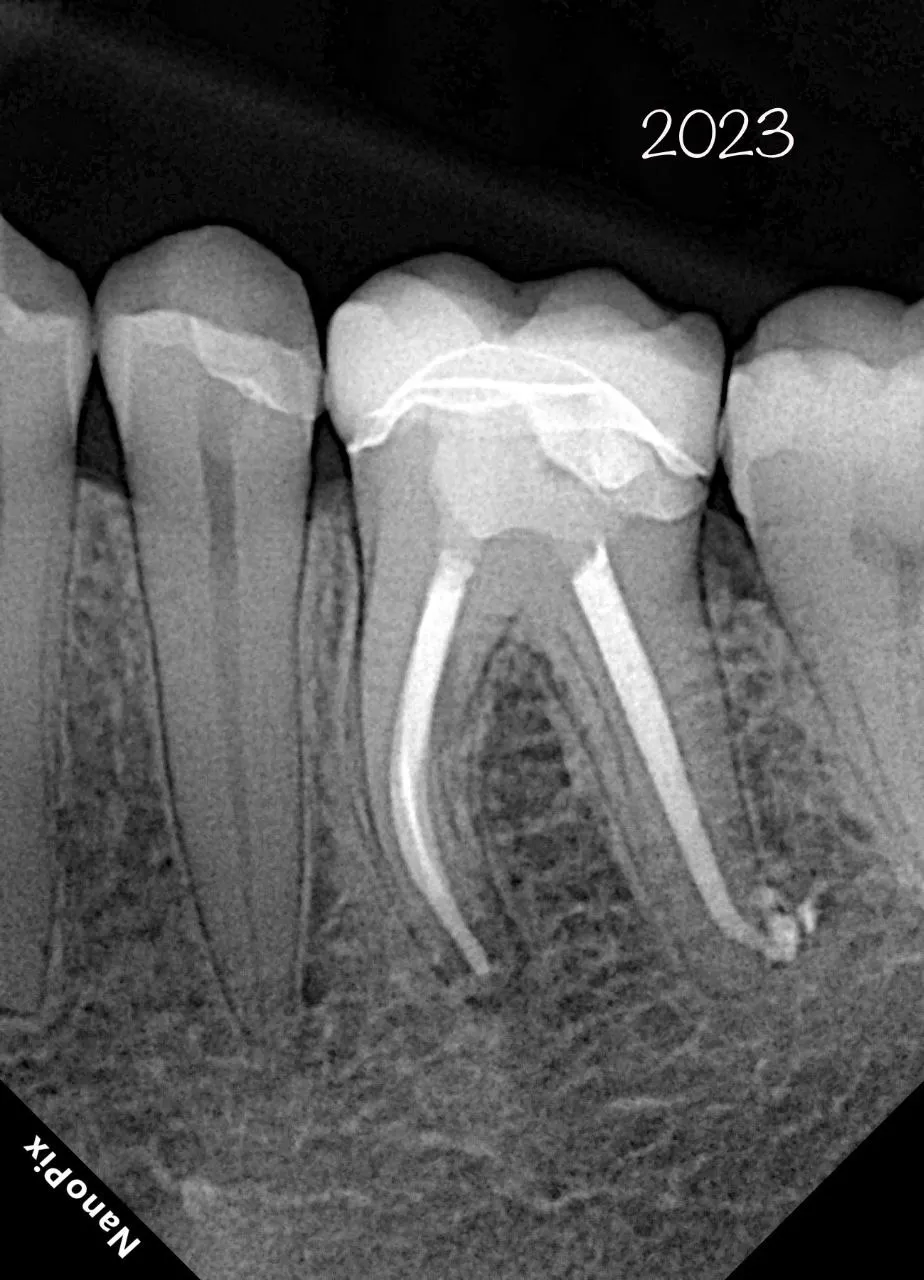

Профессионалы о нашей продукции

Мы тщательно следим за качеством нашей продукции и предлагаем только надежную технику, что без соменения производит впечатление на профессионалов в области эндонтии. Здесь вы можете увидеть те самые, искренние и настоящие отзывы наших клиентов.